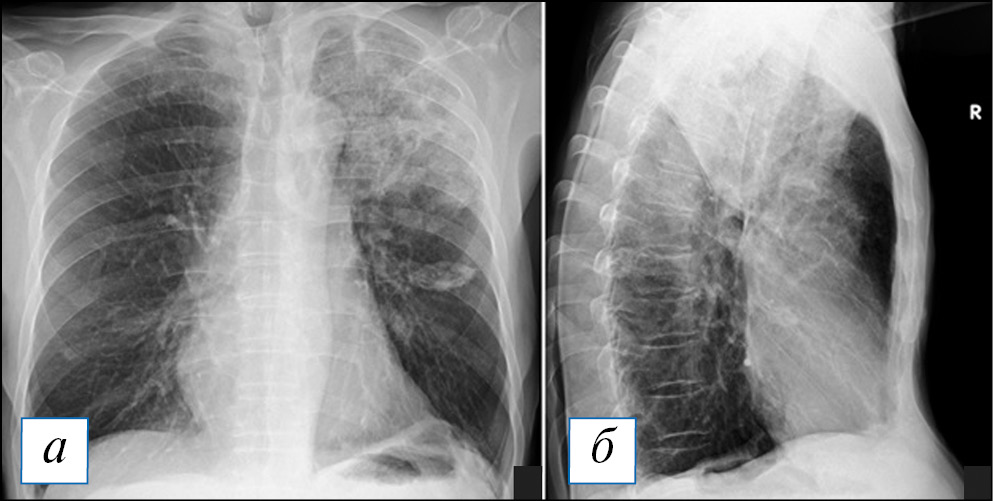

По данным лучевых методов диагностики выявляют отграниченную полость или полость с небольшим количеством перикавитарной инфильтрации. Полость имеет «бухтообразные» внутренние контуры, в ее просвете можно наблюдать жидкость с горизонтальным уровнем и отдельно лежащие секвестрированные фрагменты легкого (рис. 17, 18). При динамическом наблюдении может отмечаться формирование секвестров из краевых отделов полости. Отграниченность процесса по данным рентгенографии или КТ — важнейший дифференциальный признак отличия гангрены от гангренозного абсцесса. Во всех случаях при подозрении на гангрену легкого или гангренозный абсцесс необходимы госпитализация больного, энергичная антибиотикотерапия и наблюдение торакальным хирургом из-за большой вероятности развития легочных кровотечений в данной группе больных.

Рис. 17. Компьютерная томография органов грудной клетки в аксиальной (а–г) и сагиттальной (д) проекциях. Гангренозный абсцесс в верхней доле левого легкого. С двух сторон в верхних долях наблюдается инфильтрация, на фоне которой слева имеется крупная полость с четкими контурами, внутри — формирующийся секвестр. [Изображения из архива авторов]. / Fig. 17. Axial (а–г) and sagittal (д) chest CT images. Gangrenous abscess in the upper lobe of the left lung. On both sides, there is infiltration in the upper lobes, against the background of which there is a large cavity with clear contours on the left, and a sequester is forming inside. [Images from the authors’ archive].

Рис. 18. Рентгенограмма органов грудной клетки в прямой (а) и правой боковой (б) проекции того же больного, что и на рис. 17. В верхней доле слева хорошо видно неоднородное отграниченное затенение, однако достоверно судить о формировании на этом фоне секвестра затруднительно. [Изображения из архива авторов]. / Fig. 18. Chest X-ray of the same patient one presented as in Fig. 17. In the upper lobe on the left, a non-uniform limited opacity is clearly visible, however, it is difficult to reliably judge the formation of the sequester against this background. [Images from the authors’ archive].

ЗАКЛЮЧЕНИЕ